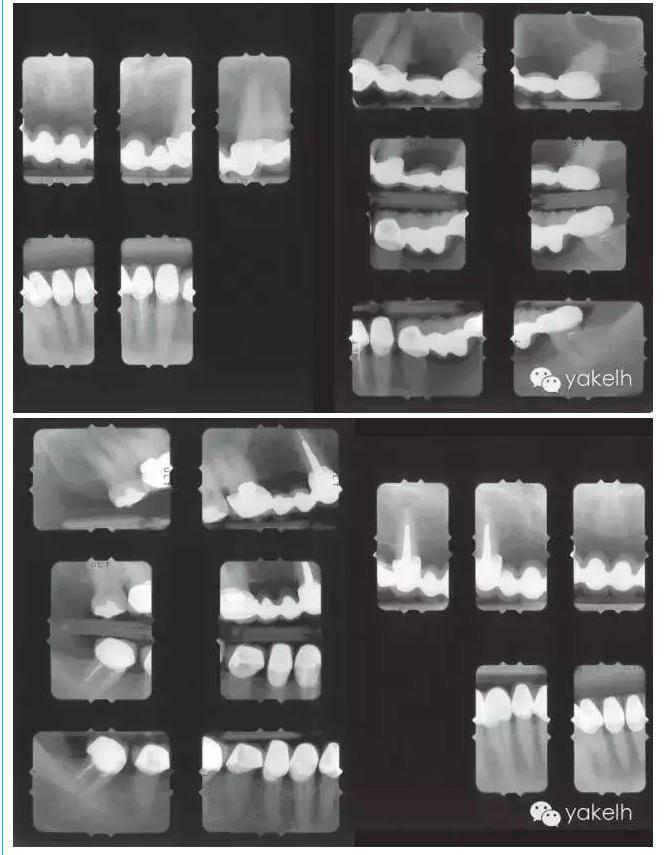

¤¤因關(guān)鍵基牙遠(yuǎn)期預(yù)后較差,臨床上經(jīng)常需要將牙支持式固定橋換成種植體支持式固定橋。治療的困難在于整個(gè)治療過程中因?yàn)榛颊卟荒芙邮芑顒?dòng)的暫時(shí)修復(fù)體,需要制作固定的暫時(shí)修復(fù)體。該患者在其他國家進(jìn)行了整個(gè)牙合重建。但對(duì)結(jié)果不滿意,也不喜歡美學(xué)效果,上唇過于凹陷,咬合也不舒適。此外,修復(fù)體結(jié)構(gòu)和邊緣適合也不足,需要全部更換。部分牙齒缺失,并且關(guān)鍵基牙—右上尖牙,遠(yuǎn)期預(yù)后差。因此,治療計(jì)劃包括植骨在內(nèi)的口腔種植手術(shù)。

1400.png

1401.png

1402.png

1403.png

1404.png

1405.png

1406.png

1407.png

1408.png

1409.png

1410.png

1411.png